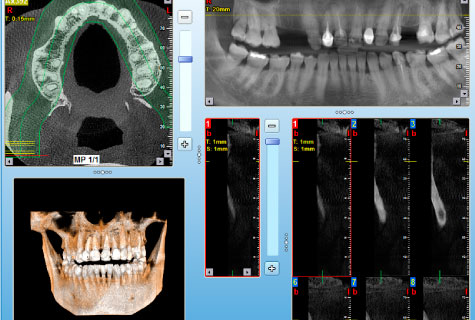

- Único que incluye programa para colocación de implantes virtual.

- Marcación del dentario inferior para un mejor diagnóstico.

Tomografía Cone Beam

- Tomografía de maxilares

- Tomografía ATM

- Tomografía Macizo Facial

- Tomografía senos paranasales

- Tomografía de sector